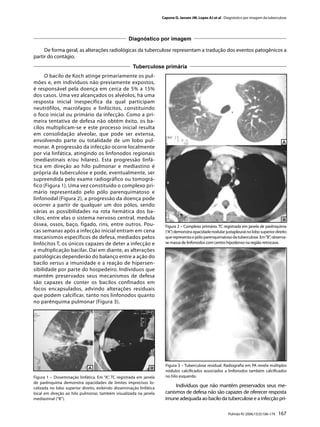

fico (Figura 1). Uma vez constituído o complexo pri-

linfonodal (Figura 2), a progressão da doença pode

óssea, ossos, baço, fígado, rins, entre outros. Pou-                   Figura 2 – Complexo primário. TC registrada em janela de parênquima

cas semanas após a infecção inicial entram em cena                     (“A”) demonstra opacidade nodular justapleural no lobo superior direito

mecanismos específicos de defesa, mediados pelos                       que representa o pólo parenquimatoso da tuberculose. Em “B”, observa-

linfócitos T, os únicos capazes de deter a infecção e                  se massa de linfonodos com centro hipodenso na região retrocava.

Figura 3 – Tuberculose residual. Radiografia em PA revela múltiplos

nódulos calcificados associados a linfonodos também calcificados

Figura 1 – Disseminação linfática. Em “A”, TC registrada em janela     no hilo esquerdo.

de parênquima demonstra opacidades de limites imprecisos lo-

calizada no lobo superior direito, exibindo disseminação linfática

Indivíduos que não mantêm preservados seus me-

local em direção ao hilo pulmonar, também visualizada na janela        canismos de defesa não são capazes de oferecer resposta

mediastinal (“B”).                                                     imune adequada ao bacilo da tuberculose e a infecção pri-